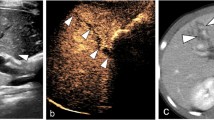

Gross pathology showed that 10 dogs had incurred grade III renal trauma, and 15 had incurred grade IV trauma. Prior to shock, all kidneys were fully functional and flexible. With the onset of shock, the kidneys became smaller (Fig. 1) and softer and had a pale cortex and dark red medulla; further, the cortical vessels became constricted and less flexible.

Gross pathology, CEUS, and CECT images of grade III renal trauma with active bleeding at baseline are shown in Fig. 3a–c and in mild shock are depicted in Fig. 3d–f. Figure 3g–i shows images of grade III renal trauma with active bleeding in moderate shock and Fig. 3j–l is images for grade IV renal trauma with active bleeding in severe shock.

(a–c) Gross pathology, CEUS, and CECT images of grade III renal trauma with active bleeding (yellow arrow) at baseline; (d–f) gross pathology, CEUS, and CECT images of grade III renal trauma with active bleeding (yellow arrow) in mild shock; (g–i) gross pathology, CEUS, and CECT images of grade III renal trauma with active bleeding (yellow arrow) in moderate shock; (j–k) gross pathology, CEUS, and CECT images of grade III renal trauma with active bleeding (yellow arrow) in severe shock. CEUS contrast-enhanced ultrasonography, CECT contrast-enhanced computed tomography

Before shock, the kidneys were brightly colored, with an intensive cortical vascular distribution and a steady pulse (Fig. 3a). Overall, 76 % (19/25) of the dogs showed renal trauma on conventional US, but accurate classification was not possible. In contrast, CEUS showed constriction of the renal arteries within the trauma region at all stages of shock, with the region of trauma being either not enhanced or only weakly enhanced. Trauma diagnosis by CEUS was 80 % accurate for grade III (8/10) and 100 % accurate for grade IV (15/15) traumatic incisions. During active bleeding, visible contrast agent flowing out from the rupture in the renal capsule was considered to indicate either no or low contrast enhancement (Fig. 3c).

Gross examination showed no bleeding in any of the 25 wounds during the stage of severe shock (Fig. 3j). CEUS showed that with progressive shock, the flow of the contrast agent slowed significantly, and arteries at all depths became more constricted. The contrast agent slowly filled the renal capsule, accumulated in the vascular endings, and dispersed, resulting in reduced intensity of contrast enhancement and extended WT. During the stage of severe shock, perfusion of the renal parenchyma declined, and the intensity of contrast enhancement decreased. The diagnostic sensitivity of CEUS declined to 60 % for grade III (6/10) and 80 % for grade IV trauma (12/15) (Fig. 3e, h, k).

Comparison of CEUS and CECT results

On CECT examination, the renal lesion appeared as a low attenuation area when the kidney capsule was incomplete, and active bleeding appeared as high attenuation areas (Fig. 3c). During the baseline and mild shock stage, sonograms obtained after the intravenous injection of contrast agent showed marked contrast medium extravasation and pooling at the site of active bleeding (Fig. 3b, e). Graded hypotension resulted in a significant, stepwise diminution in renal blood flow on both CEUS and CECT. As shown in Table 2, no significant difference was found in the shock detection rate between CEUS and CECT during any stage of shock (P > 0.05). CECT imaging showed kidney shrinkage, with a decrease in both the areas of enhancement and irregular non-enhanced areas (Fig. 3f, i, l).